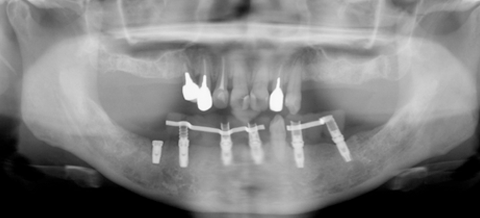

初診時

患者様は、女性40代、上下顎の歯が グラグラで食事がほとんどできない状態で来院されました。

歯周病の検査をすると特に下顎は歯を支えている骨は、ほとんど吸収してしまっている状態でした。患者様のご希望は、「きちんと噛めるようになりたい。再治療を繰り返すようなことはしたくない。将来的にも不安がない治療を行いたい。」とうことでした。

下顎は1歯を残して全て抜歯と診断しました。患者の希望を最優先に考えると、歯を無理に残すことで治療が複雑になり、逆に治療計画が難しくなってしまい将来的にかなり大きな再治療が必要になり、抜歯と診断しました。